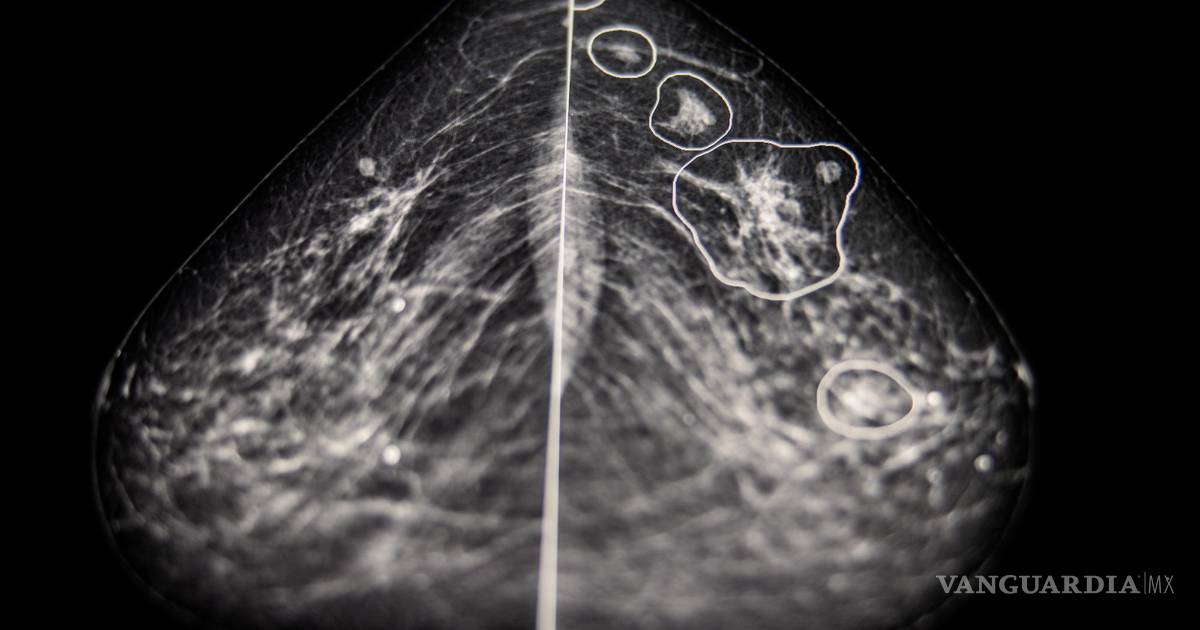

En el interior de una habitación oscura del Hospital del Condado de Bács-Kiskun en la periferia de Budapest, Éva Ambrózay, una radióloga con más de veinte años de experiencia, observaba un monitor de computadora que mostraba la mamografía de una paciente.

Dos radiólogos ya habían dicho que la radiografía no mostraba ningún signo de que la paciente tuviera cáncer de mama. Pero Ambrózay observaba atentamente varias zonas del escáner marcadas en rojo, que el programa de inteligencia artificial había señalado como potencialmente cancerosas.

A partir de los millones de casos que recibe el sistema, la tecnología crea una representación matemática de las mamografías normales y las que presentan cáncer. Gracias a su capacidad para analizar cada imagen de manera más detallada que el ojo humano, compara esa referencia para detectar anomalías en cada mamografía.

El año pasado, después de hacer pruebas con más de 275 mil casos de cáncer de seno, Kheiron informó que su programa de inteligencia artificial igualaba el desempeño de los radiólogos humanos cuando se usaba para una segunda interpretación. Además, reducía la carga de trabajo de los radiólogos en al menos un 30 por ciento, ya que disminuía el número de radiografías que tenían que leer. En otros resultados obtenidos el año pasado en una clínica húngara, la tecnología aumentó la tasa de detección de cáncer en un 13 por ciento porque se identificaron más tumores malignos.

En el Hospital del Condado de Bács-Kiskun en la periferia de Budapest, Ambrózay comentó que al principio dudó de la tecnología, pero se convenció muy poco tiempo después. Mostró la radiografía de una mujer de 58 años con un pequeño tumor detectado por la inteligencia artificial que a Ambrózay le costaba ver.

Esta tecnología identificó algo, dijo, “que pareció salir de la nada”.